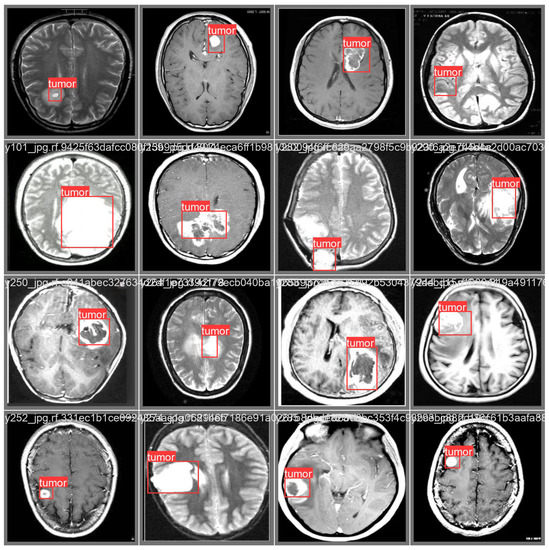

3.3. Prediction Examples